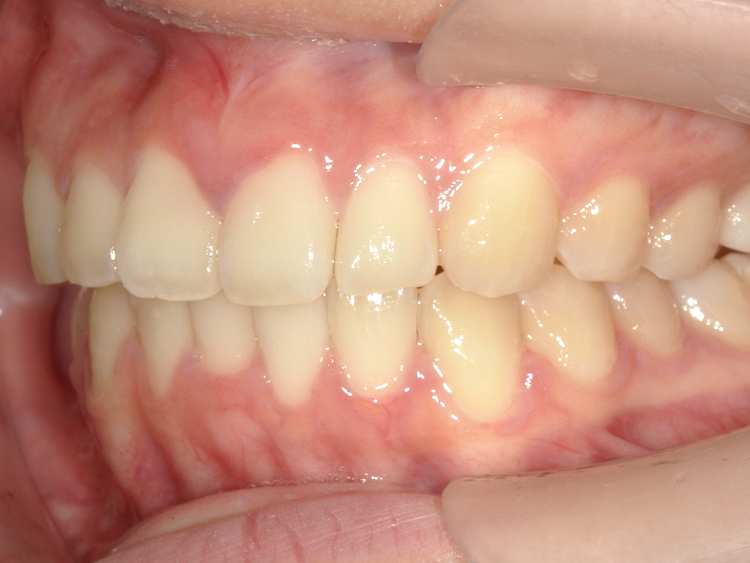

After

| 主訴 | 上前歯の突出を治したい (出っ歯を治したい) |

|---|---|

| 年齢 | --- |

| 治療 期間 |

約5ヶ月 |

| 治療 内容 |

インビザラインiGoで上顎のみ治療。 前歯の歯と歯の間をごく少量削り、 前に出ている歯が入るスペースを作り、綺麗に揃えた。 |

| 治療費 | ¥352,000(税込)+月額調整料 |

| 治療のリスク | 歯と歯の間を削ることでスペースを確保するので、 場合によっては歯が染みる症状が出ることがある。 |